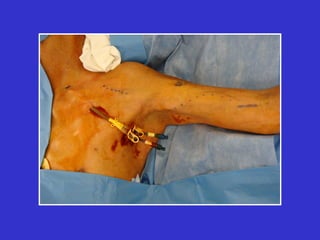

Femoral Vein Transposition

• 2 year primary patency of 75%.

• 2 year secondary patency of 94%.

• High risk of steal. Limit

anastomosis to 4-5mm.

• Patients with PVD are not

candidates.

• High flows (2000 ml/min) may

exacerbate CHF.

Caveat for leg access

• Exhaust all upper extremity-Last ditch

means last ditch

• Objective documentation of arterial

perfusion, pvrs with toe pressures

• Preserve CFV, profunda femoris

• Mild Chronic limb swelling is common

• Anticoagulate 3-4 months

• Amputation is not absolute

contraindication to leg access